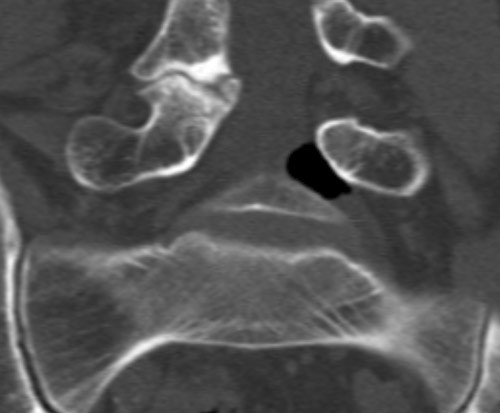

A man in his 60s was admitted to hospital with a two-day history of left-sided ischialgia and paresis development in L5 nerve innervated muscle. MRI showed a formation in the left lateral recess at L4/L5 level with dorsal dislocation of the left L5 nerve root. The formation had an unusually low MR signal giving rise to suspected calcification or the presence of air. A supplementary CT scan showed a well-defined collection of air in the same area (see images).

Clinical deterioration led to surgical exploration of the L5 root. Ventrally to the L5 root an amount of air was observable encapsulated in epidural soft tissue; an incision was made and the air released. Following this, the L5 root was softer to palpation and had free movement. The patient experienced considerable improvement postoperatively.

The presence of air in the intervertebral discs, known as the vacuum phenomenon, is a relatively common radiological finding in cases of degenerative changes in the lumbar spine. Cases are reported in the literature of gas in the spinal canal, in intervertebral foramina, in prolapsed tissue, epidurally and subarachnoidally, associated with the vacuum phenomenon (1). It may also occur secondary to degeneration in facet joints and ligaments.

In our patient, there was only low grade disc herniation without rupture in the anulus fibrosus and slight facet joint arthrosis at the levels concerned. The air may represent gas formation from a sequestrum from an earlier prolapse, alternatively a gas-containing pseudocyst associated with the vacuum phenomenon in adjacent intervertebral disc spaces. It is difficult on this basis to explain the acute onset case history, but incision and release of the air build-up in the patient was nevertheless therapeutic.